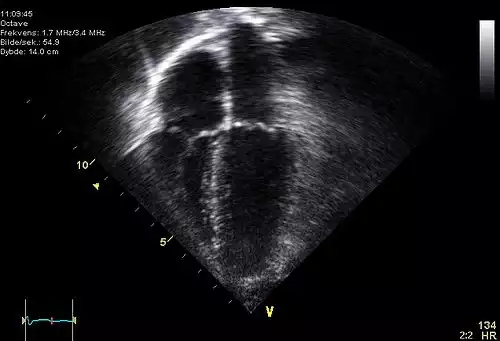

اکوکاردیوگرافی ( به انگلیسی: Echocardiography ) یا پژواک نگاری قلب که به آن "سونوگرافی قلب" یا "اکوی قلب" هم گفته می شود روشی غیر تهاجمی است که با استفاده از امواج صوتی، ساختمان داخلی قلب به تصویر کشیده می شود و در حقیقت به عنوان استاندارد تشخیص بیماری های قلبی تلقی می شود.

در این روش از سونوگرافی استاندارد دو بعدی، سه بعدی و داپلر برای ایجاد تصاویر از قلب استفاده می شود.